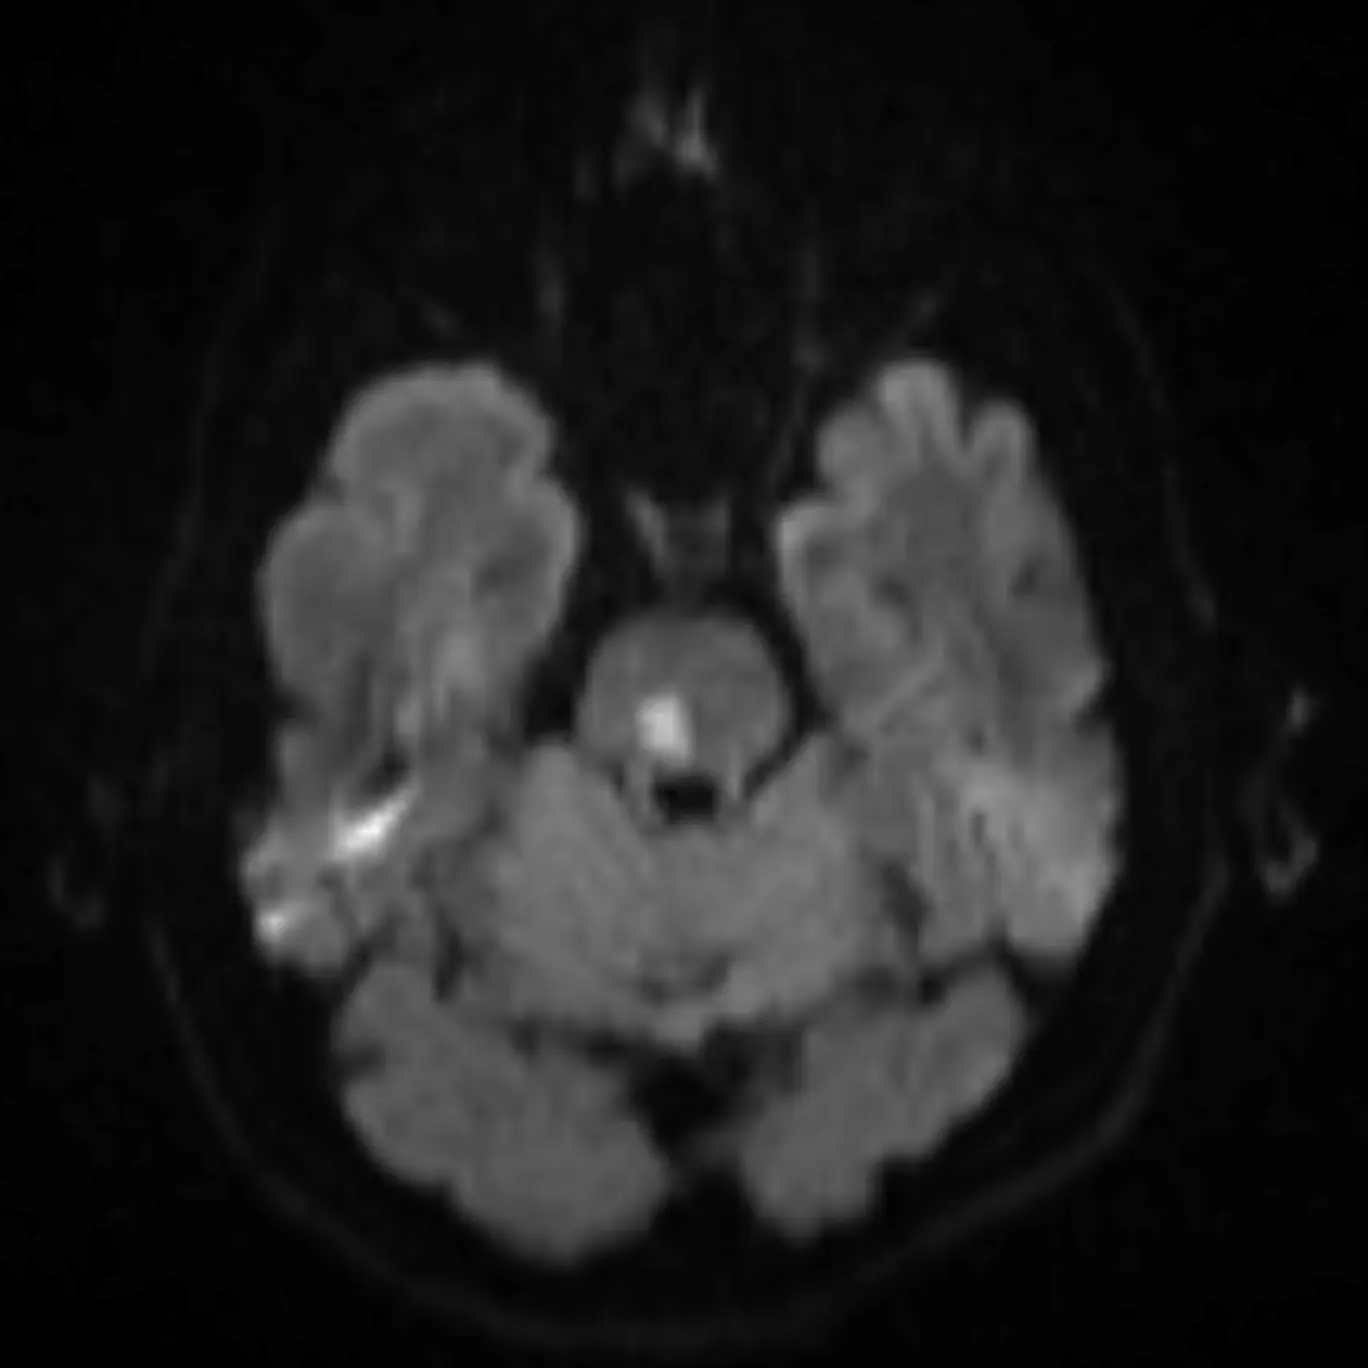

3. Decussation of the superior cerebellar peduncles

The superior cerebellar peduncles are seen in the next section, but they cross at this level in the center of the midbrain as the fibers travel superiorly.

The fibers of the superior cerebellar peduncles are highly organized causing water molecules to move along the myelin sheaths in relatively uniform directions (i.e. anisotropy). This often causes mild physiologic diffusion restriction that may be misinterpreted as an infarction. Nonetheless, infarction in this region can occur characterized by bilateral cerebellar ataxia called Wernekinck commissure syndrome, which is highly unlikely without supporting clinical history. Absence of this decussation occurs in Joubert syndrome and other ciliopathies, producing a "molar tooth" appearance of the midbrain.